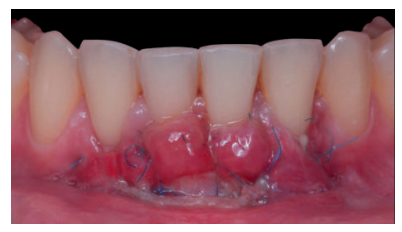

Previamente a la intervención, la paciente se enjuagó durante un minuto con un colutorio de clorhexidina. La técnica quirúrgica comenzó con la preparación del lecho receptor, se realizaron incisiones intrasulculares a nivel cervical hasta la línea ángulo de todos los dientes del frente antero-inferior (33-43), desinsertando la base de la papila sin seccionarla con la ayuda de instrumentos de tunelización. Posteriormente se realizó una incisión en el fondo de vestíbulo (Figura 11). A continuación, se obtuvo un injerto de tejido conectivo del paladar introduciéndolo en el lecho receptor, siendo todas las suturas realizadas de la misma manera que en el caso clínico 1, usando tanto material reabsorbible como no reabsorbible de 5/0 y 6/0 ceros (Figura 12).